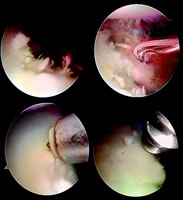

本报讯(通讯员 蒋锐)第三军医大学西南医院关节外科中心副主任唐康来博士等,在总结国内外最新研究成果的基础之上,设计了一种新的手术方式——关节境下带线锚钉双重垂直褥式缝合修复Bankart损伤治疗肩关节习惯性脱位,经过两年多的临床实践,治疗了10例患者,均取得了良好的临床效果。

手术改进主要表现在:①将3枚铆钉减少为2枚,节约了成本,方法更为简单,手术时间明显缩短;②采用双重垂直褥式缝合修复Bankart损伤,双重垂直褥式缝合较国外同行使用的边对边缝合牢固稳定性更为可靠;③同时将前下方的关节囊向前上转移,关节镜下完成了以往只有在开放条件下才能完成的步骤,缩短了手术康复的时间。

图1:前方盂唇损伤

图2:清理

图3:锚钉固定

图4:修复盂唇损伤, http://www.100md.com